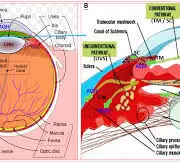

A study assessed the effect of an intensive initial IOP lowering treatment strategy on the progression of visual field damage. A total of 242 patients with newly detected early or moderate untreated open-angle glaucoma were enrolled at two university hospitals in Sweden. Participants were randomly allocated (1:1) to either initial treatment with intensive IOP-lowering medications followed by 360° laser trabeculoplasty (LTP), or to traditional mono-therapy, which was increased when deemed necessary. The primary study outcome of interest was the predicted remaining visual field, as measured by the visual field index (VFI) at projected end of life. Results: The median untreated IOP was 24 mmHg in both treatment groups. During follow-up, median and mode IOP was 17 mmHg in the mono- and 14 mmHg in the multi-treated group. In the mono-treated group the median VFI at projected end of life was 79.3%, and in the multi-treated group 87.1%, p=0.15. Annual rate of progression of visual field damage was faster in mono-treated than in multi-treated participants; median losses per year were 0.65 and 0.25 percentage units respectively, p=0.09. Progression events occurred in 21% of the mono- and in 11% of the multi-treated participants, p=0.03. Adverse events, mostly mild, were reported in 25% of the mono-, and in 36% of the multi-treated participants. Differences in visual field outcomes between treatment groups were more pronounced in participants having higher baseline IOP defined by median split of untreated IOP values. In the overall analysis the visual field outcomes were not overwhelming better in the multi-treated group, but post-hoc analysis showed definite benefit in patients with higher untreated IOP. Based upon the results of this study, initial intensive treatment may be considered in glaucoma patients with high untreated IOP at diagnosis, while we found no evidence that multi-therapy should be given routinely to all glaucoma patients.